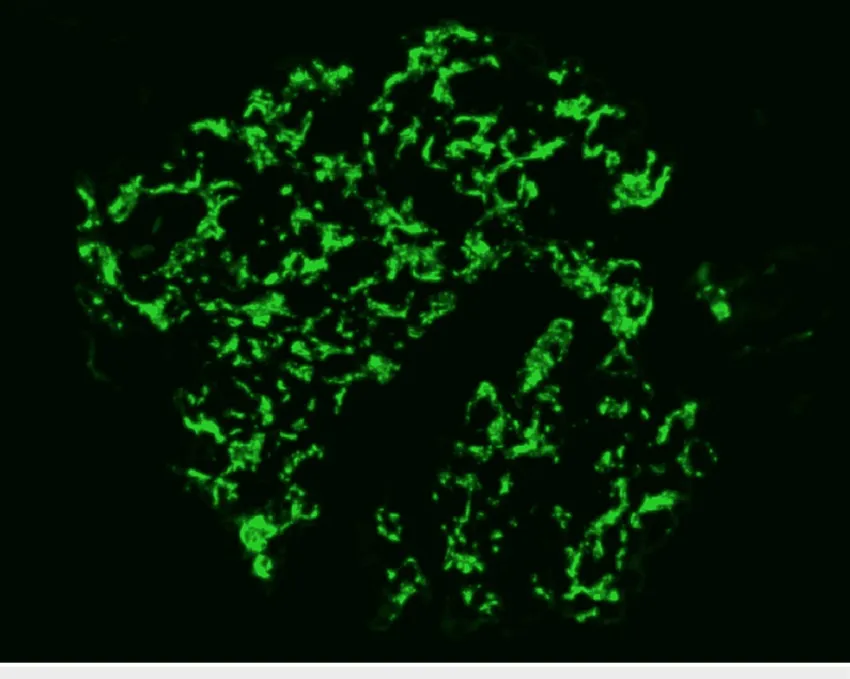

Figura 1. Imagens da biópsia renal. (A) Microscopia óptica mostrando hipercelularidade mesangial difusa, sem crescents, necrose ou cicatrizes segmentares. Discreta fibrose intersticial e atrofia tubular (HE). (B) Imunofluorescência evidenciando forte marcação de C3 no mesângio e nas alças capilares. (C) Microscopia eletrônica demonstrando depósitos mesangiais e depósitos subepiteliais maiores. Observa-se apagamento difuso dos pedicelos e afinamento das membrana basal glomerular (250 nm de espessura).

A presença de proteinúria moderada em paciente jovem, com imunofluorescência mostrando deposição dominante de C3 e depósitos densos à microscopia eletrônica, aponta para GNC3.

Seis anos depois, já em outro serviço, a paciente reaparece com creatinina 1,6 mg/dL e proteinúria 1,3 g/g. Revisão da biópsia confirmou o diagnóstico de GNC3, corrigindo o equívoco inicial…